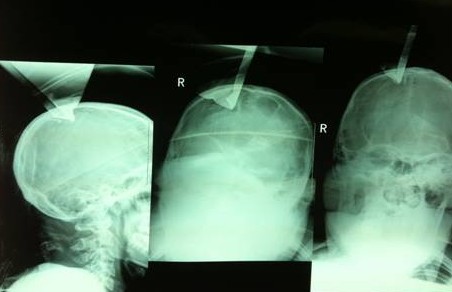

我们先看看这个患者的片子,从片子上很明显,钢板穿过了右顶骨造成开放性骨折。